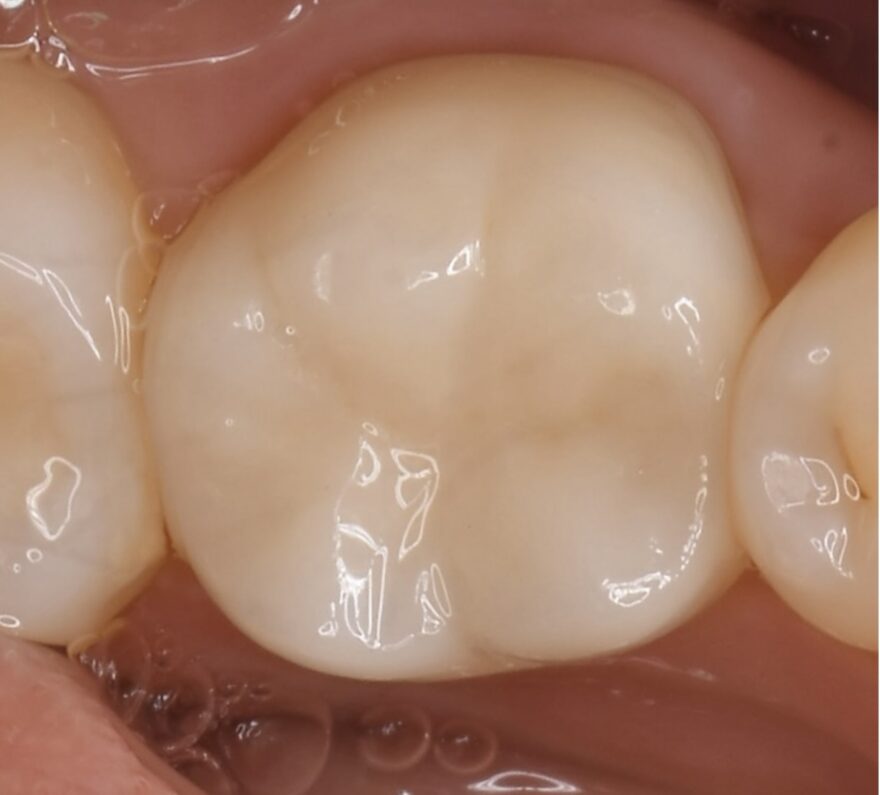

噛み合わせに関与している部分が失われてしまったため、セラミッククラウンを被せる必要があります。

保険適応のレジン充填(光硬化型のプラスチック)を詰めても、強度に劣るため、咬合力に耐えれず、染みてしまい、しっかり噛むことができません。

セラミックは銀歯とは異なり、しっかりお手入れをし、定期検診に来ていただくことで、10年20年と長持ちします。

尚、部分的な詰め物タイプのセラミック(セラミックインレー)は8年前後で割れてしまう可能性があるため、当院では行っていません。

この症例の治療費

奥歯用スタンダードセラミック 110,000円(税込)

この症例のリスク

稀にセラミックが割れたり外れることがあります。

その場合は5年保証が付いているため、速やかに無料対応させて頂きます。